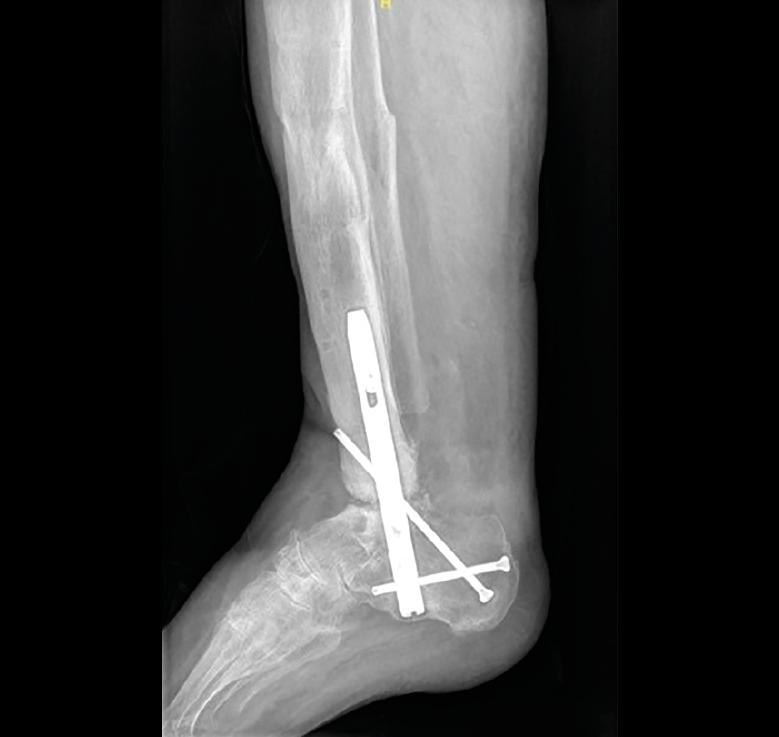

El paciente con antecedente de fractura de pilón tibial presentaba una pseudoartrosis del foco de fractura metafisario con antecedentes de infección de la osteosíntesis previa. Optamos, una vez tratada y curada la infección, por el clavo retrógrado como método de tratamiento de ambas lesiones, la pseudoartrosis de la fractura y la degeneración articular grave. Aunque se consiguió la consolidación del foco de fractura y la fusión de la articulación subtalar, la artrodesis del tobillo no se consiguió. No precisaba ayuda para la marcha y el dolor mejoró de 8 a 2 al año de evolución (Figura 1).